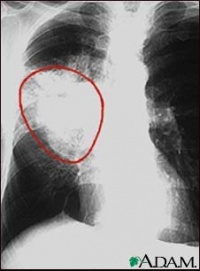

非小细胞肺癌(Non-Small Cell Lung Cancer, NSCLC)是肺癌最常见的组织学类型,约占肺癌总数的 85%。与小细胞肺癌(SCLC)相比,NSCLC 的倍增时间较长,生物学行为相对惰性。NSCLC 并非单一疾病,而是一组异质性肿瘤的统称,主要包括肺腺癌肺鳞癌和大细胞癌。随着精准医学的发展,NSCLC 的治疗已从传统的“手术+放化疗”模式,彻底转变为基于驱动基因(如 EGFR, ALK)的靶向治疗和基于 PD-L1 表达的免疫治疗模式。根据最新的 NCCN Guidelines (v1.2026),“围手术期免疫治疗”(Chemo-IO)已确立为可切除 II-III 期患者的标准治疗。

肺鳞癌

(~30%)

• 多位于肺中心(中央型),易空洞

• 与吸烟高度相关